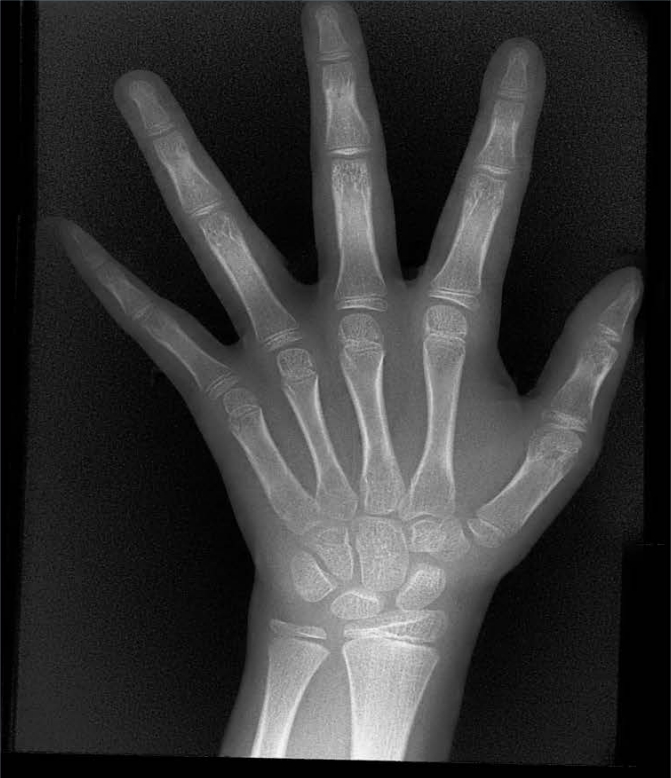

X射線骨齡儀通過拍攝兒童手腕部(指骨、掌骨、腕骨)的X射線影像,依據(jù)骨骼的形態(tài)、大小、鈣化程度等特征,結(jié)合評估標(biāo)準(zhǔn)(如《中國青少年兒童手腕骨成熟度及評價方法》,簡稱《中華-05》標(biāo)準(zhǔn))進行骨齡判定。相較于傳統(tǒng)檢測方式,X射線骨齡儀具有輻射劑量低、影像清晰度高、檢測效率高的優(yōu)勢,能精準(zhǔn)捕捉骨骼發(fā)育的細(xì)微變化,為骨齡評估的準(zhǔn)確性提供保障。